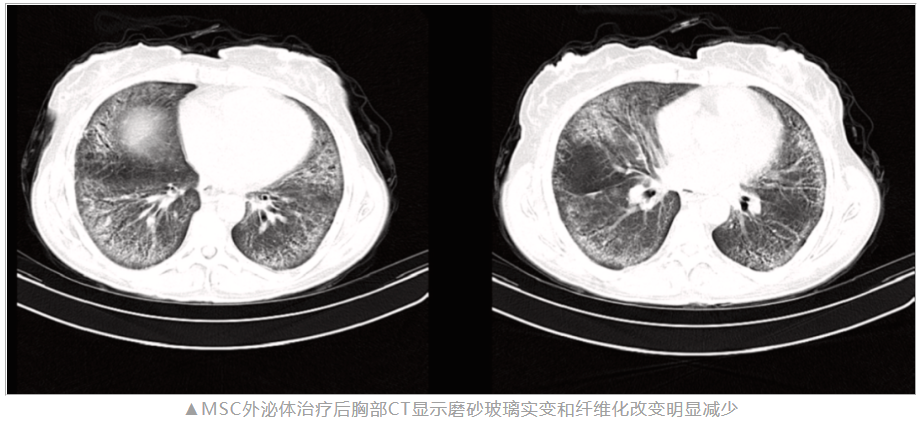

過程:患者接受了共計(jì)八次的 MSC-EVs 靜脈輸注。應(yīng)用四周后,患者反饋?zhàn)陨砗粑щy、咳嗽等癥狀得到顯著緩解。通過胸部CT掃描結(jié)果可見,肺部的玻璃樣密度以及纖維化病變均有明顯減輕。

影像學(xué)檢查結(jié)果:治療后兩個月的胸部CT掃描顯示玻璃樣密度和纖維化改變顯著減少。